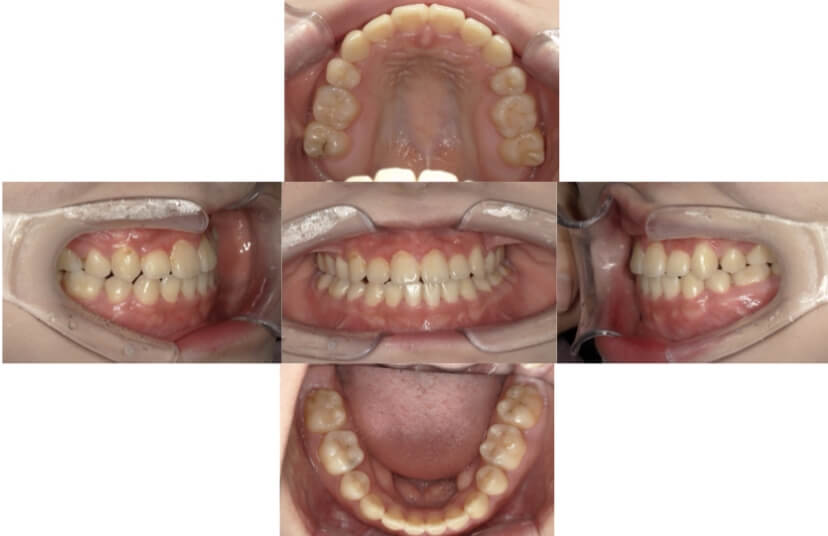

症例8

叢生

抜歯

ブラケット矯正

上下顎叢生(上下の前歯のガタガタ)のケースです。

装置はラビアル(上下表側)で、上下顎の小臼歯を4本抜歯を行っています。抜歯したスペースを使って、上下の前歯の後方移動と叢生(ガタガタ)の改善を行っています。

主訴 歯並びが悪く、舌を噛んでしまうのを治したい。

年齢・性別 27歳 男性

お住まいの地域 東京都大田区

治療方針 抜歯スペースを利用して上下前歯の叢生(ガタガタ)の改善

抜歯部位 上下顎左右第一小臼歯

使用装置 ラビアル(上下表側)、顎間ゴム

治療期間 3年1か月

治療回数 30回

リテーナー クリアリテーナー

BEFORE

治療経過